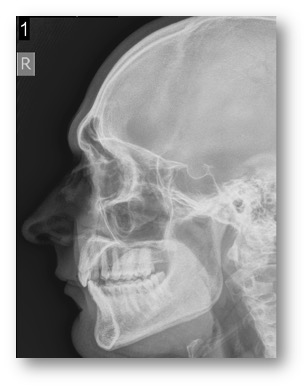

- Shaving Down Brow Ridge with Rhinoplasty

- Softening Features- Left

- Right View

- Shaving Brow Ridge